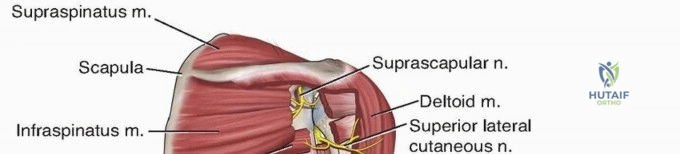

Neuromuscular Anatomy and the Radial Nerve

The radial nerve is the most critical anatomical structure at risk during both the initial injury and subsequent surgical approaches to the humerus. The nerve, accompanied by the profunda brachii artery, exits the axilla and passes through the triangular interval. This interval is bordered superiorly by the teres major, medially by the long head of the triceps, and laterally by the humeral shaft.

From the triangular interval, the radial nerve transverses from medial to lateral along the posterior aspect of the humeral shaft within the spiral groove. It pierces the lateral intermuscular septum approximately 10 to 12 centimeters proximal to the lateral epicondyle to enter the anterior compartment of the arm. Distally, the nerve travels in the anatomic interval between the brachialis muscle medially and the brachioradialis muscle laterally. This specific interval is the foundation of the distal anterolateral approach to the humerus.

The musculocutaneous nerve also requires consideration during the anterior approach. It pierces the coracobrachialis proximally, lies on the undersurface of the biceps brachii muscle, and rests superficially on the brachialis muscle. It provides motor innervation to the medial portion of the brachialis before terminating distally as the lateral antebrachial cutaneous nerve. The dual innervation of the brachialis—medial half by the musculocutaneous nerve and lateral half by the radial nerve—permits longitudinal splitting of the brachialis muscle during the anterolateral approach without causing complete denervation.